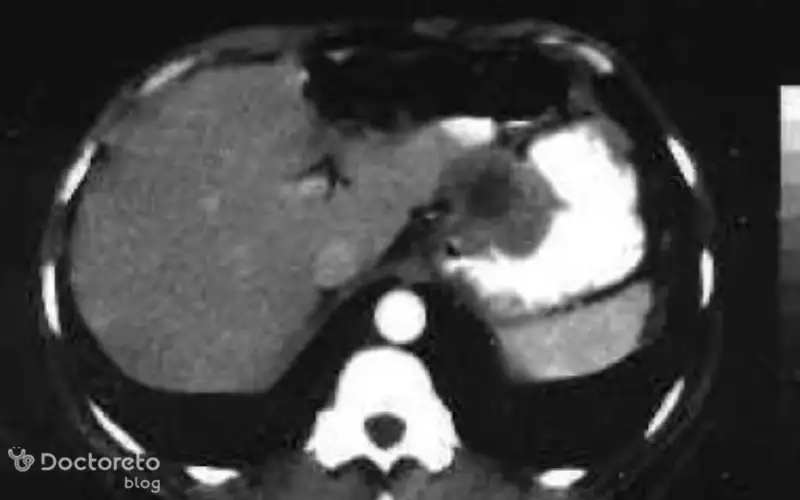

عکس تصویربرداری های سرطان معده خوش خیم

تصویربرداری پزشکی مانند سیتیاسکن و MRI به پزشکان کمک میکنند تا موقعیت، اندازه و ماهیت تومورهای معده را بررسی کنند. در ث تومورهای خوشخیم نیز این روشها کاربرد دارند تا احتمال نفوذ به بافتهای مجاور یا تبدیل احتمالی به بدخیم بیشتر و با دقت بالاتر ارزیابی شود. عکس این بخش نمونهای از این نوع تصویربرداریها را نشان میدهد.

عکس سی تی اسکن سرطان معده خوش خیم

سیتیاسکن ابزار قوی دیگری برای ارزیابی تومورهای معده است. این روش تصویربرداری به ویژه در تشخیص اندازه، موقعیت و ارتباط آنها با ساختارهای اطراف کاربرد دارد. حتی برای سلولهای خوشخیم سرطانی هم سیتیاسکن اطلاعات ارزشمندی در مورد چگونگی رشد و وضعیت بیمار ارائه میدهد. استفاده از این تصاویر کمک میکند تا پزشک نگاهی دقیقتر به تومور معده داشته باشد.